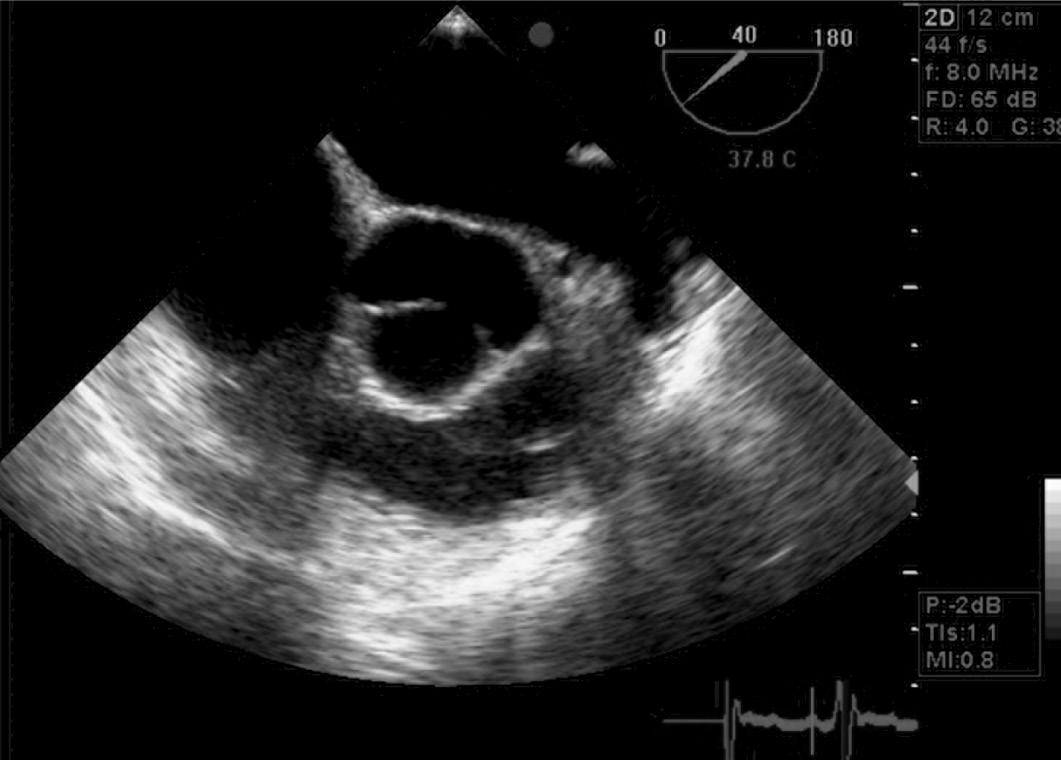

18 O Ecocardiograma no Manejo do Paciente Crítico, 193 Rodrigo Ferraz Salomão • Flávia Guimarães Brasil • Eduardo Boetner